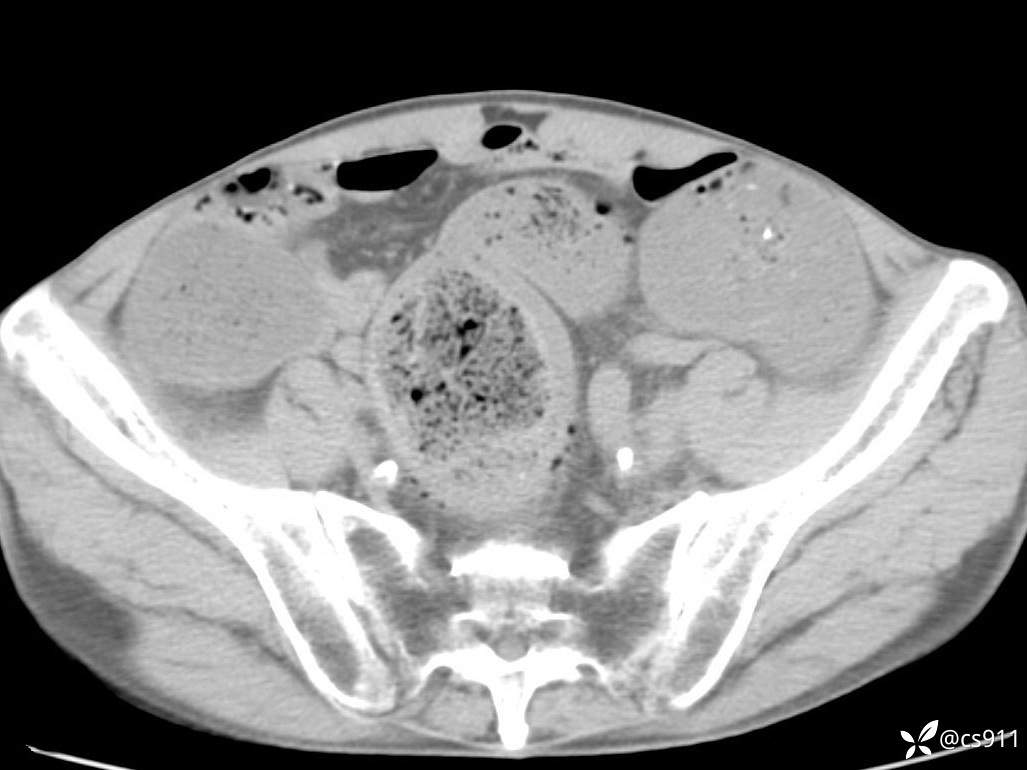

急腹症之急诊CT,原因?答案公布

男,77岁,腹痛、腹胀伴恶心呕吐1天。呕吐胃内容物,非喷射性呕吐,有咖啡色样胃内容物,诉有胃穿孔病史。查体:全腹平,下腹部压痛,全腹无反跳痛,叩诊呈浊音,移动性浊音阴性,肠鸣音减弱,1-2次/分。肛检:直肠未扪及明显肿物,可触及大量粪块。

血淀粉酶(AMY) HH 1859 U/L 35-135